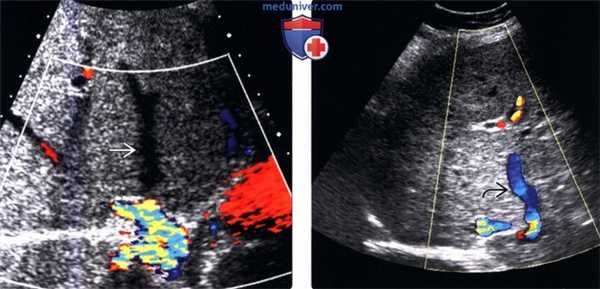

о Расширение печеночных вен с наличием двунаправленного кровотока («туда и обратно»), обнаруживаемого при допплерографии

(Слева) На аксиальной сонограмме у этой же пациентки определяется резкое расширение позадипеченочной части нижней полой вены и печеночных вен в месте впадения их в НПВ. (Слева) На сонограмме правой печеночной вены с использованием допплеровского датчи -ка определяется выраженный фазовый спектр.

(Справа) На сонограмме главного ствола воротной вены (допплерография) в этом же случае определяется увеличение пульсовых волн. Расширение нижней полой вены, печеночных вен, отек стенки желчного пузыря в сочетании с явным фазовым кровотоком в печеночных венах и повышенной пульсацией воротной вены являются классическими сонографическими признаками пассивного венозного полнокровия и ключевым моментом, позволяющим отличить это состояние от острого холецистита.

о Цветовая допплерография; для определения природы заболевания сердца - МРТ